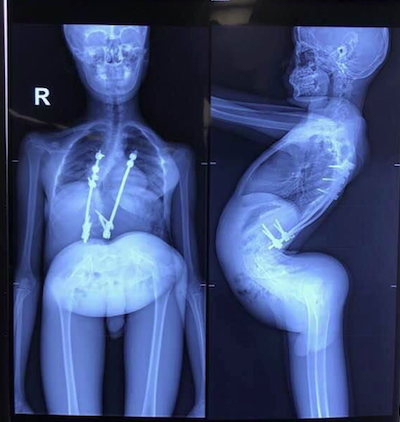

患有先天脊椎畸形的八岁中国男孩Jackson曾经被遗弃在中国街头并且在一所位于湖南省的孤儿院呆了数年。在2015年,他初次感受到了家庭的温暖。Maurita和Terence,一对在中国工作的来自澳大利亚的夫妇,把Jackson带回来了家,忐忑地等待着这位男孩的第一次大手术。

Jackson即将面临的手术由中国儿童医疗基金会提议和组织。手术的目的是为了使Jackson从老旧的医疗装置中解救出来,使他再也不用依靠轮椅来进行日常活动。

在基金会介入之前,Jackson的治疗计划主要由当地医生负责。但此前的治疗方案并没有取得良好的效果,它甚至使得Jackson的部分肺部失去了功能。为了使男孩的情况好转,基金会从纽约派去了顶级的医疗团队。

Jackson在接受第一次手术之前 /现在的Jackson

在2016年10月31日,Jackson完成了他的第一轮手术。这场手术持续了长达九个小时。在2017年,Jackson接受了第二轮手术。从去年开始,在经历了一系列矫正训练后,Jackson迈入了他人生的一个新的阶段。现在他已经回到了学校并且甚至在他养父的指导下开始学习游泳。

Xingyu在接受基金会手术之前的脊椎。

在手术之后Xingyu的站立高度多了十厘米。